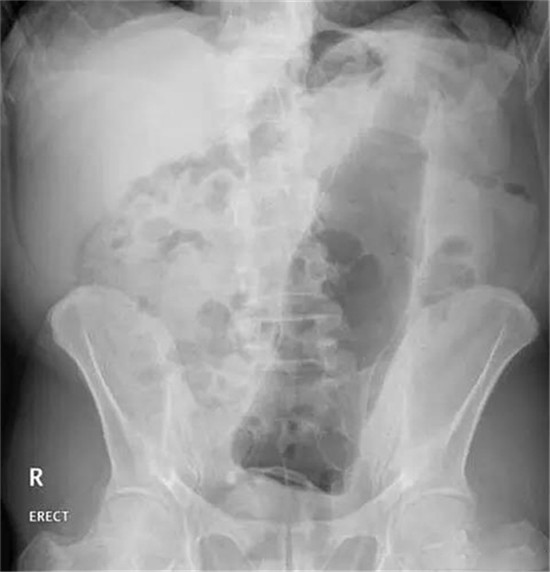

第4天,他拉不出大便。剧烈呕吐,剧烈腹痛。实在熬不住了,就去了一个大医院,但是,他隐瞒了自己把黄鳝塞进菊花的病史。

医生给他检查的时候,发现已经有腹膜炎症状,怀疑肠梗阻,拍了个片子,就是上面那个片子:一条大黄鳝在肚子里。

考虑到他已经有腹膜炎的症状,说明肠子已经有个地方破了。只能动手术了。